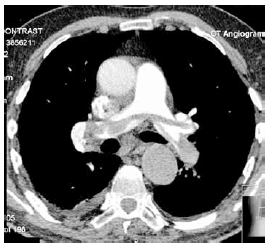

Considere a angiotomografia de tórax com contraste a seguir.

Constitui uma complicação aguda e frequente nesse paciente: